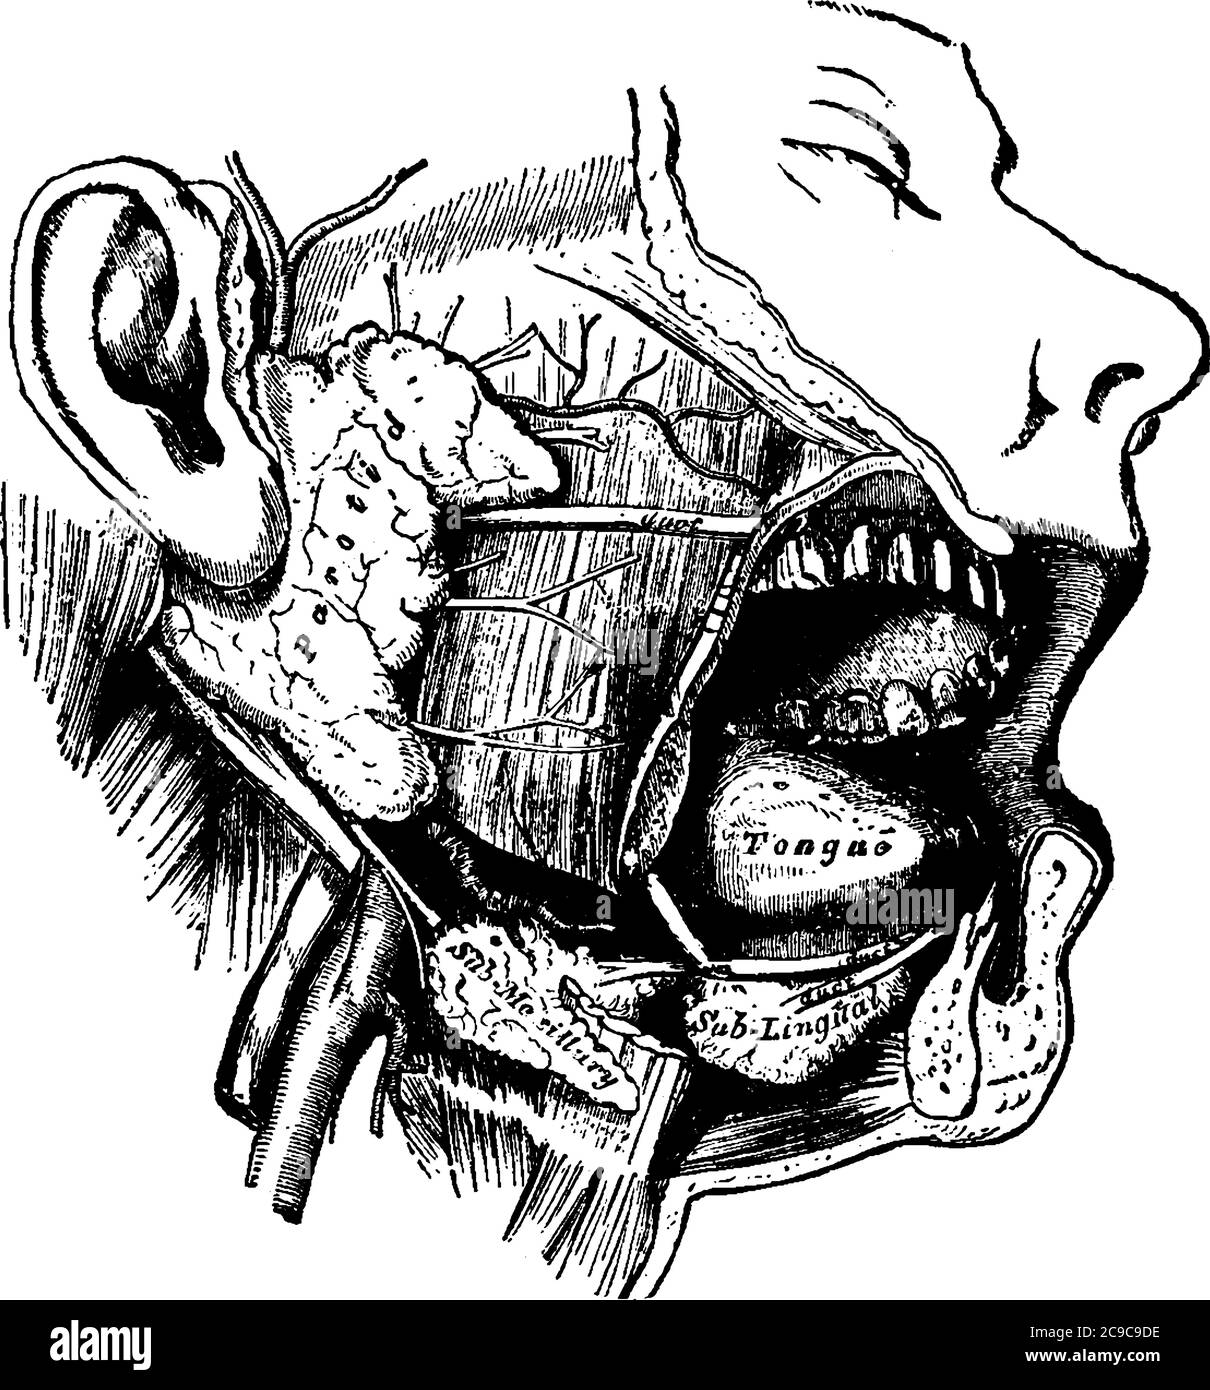

Une représentation typique des glandes salivaires humaines du côté droit, où un côté de la mâchoire inférieure a été éloigné et le visage est disséqué, Illustration de Vecteurhttps://www.alamyimages.fr/image-license-details/?v=1https://www.alamyimages.fr/une-representation-typique-des-glandes-salivaires-humaines-du-cote-droit-ou-un-cote-de-la-machoire-inferieure-a-ete-eloigne-et-le-visage-est-disseque-image367220490.html

Une représentation typique des glandes salivaires humaines du côté droit, où un côté de la mâchoire inférieure a été éloigné et le visage est disséqué, Illustration de Vecteurhttps://www.alamyimages.fr/image-license-details/?v=1https://www.alamyimages.fr/une-representation-typique-des-glandes-salivaires-humaines-du-cote-droit-ou-un-cote-de-la-machoire-inferieure-a-ete-eloigne-et-le-visage-est-disseque-image367220490.htmlRF2C9C9DE–Une représentation typique des glandes salivaires humaines du côté droit, où un côté de la mâchoire inférieure a été éloigné et le visage est disséqué,